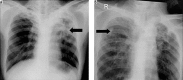

Comparison of chest X-ray lesion characteristics of multidrug-resistant tuberculosis and non-tuberculous mycobacterial infection

Purpose: This research aimed to compared chest radiographic characteristics of multidrug-resistant tuberculosis (MDR-TB) and non-tuberculous mycobacteria (NTM) infection, which can be used in early diagnostic screening.

Results: Among 538 subjects who were positive for TB during screening, 11 (2.04%) had MDR-TB, 147 (27.32%) had drug-sensitive TB, and 380 (70.63%) had NTM infection. The radiographic findings that correlated with MDR-TB were infiltrates (p = 0.010), cavities (p = 0.021), nodules (p = 0.001), and fibrosis (p = 0.010), with the best predictor of MDR-TB lesions being the presence of a nodule. The lesion locations related to MDR-TB were the upper right and left lung (p = 0.00). There were no specific lesions present in NTM infection (p < 0.05) because almost all had a meaningful correlation (p < 0.05), except the presence of a mass. The lesion location related to NTM infection was the medial aspect of the left lung (p = 0.01), and the lesion extent was also correlated (p < 0.05).

Conclusions: Chest X-ray lesion characteristics of MDR-TB show significant correlation among cavities, nodules, and fibrosis. There were no specific lesions that could differentiate NTM infection from MDR-TB; however, the most common lesion location in NTM infection was the medial aspect of the left lung.